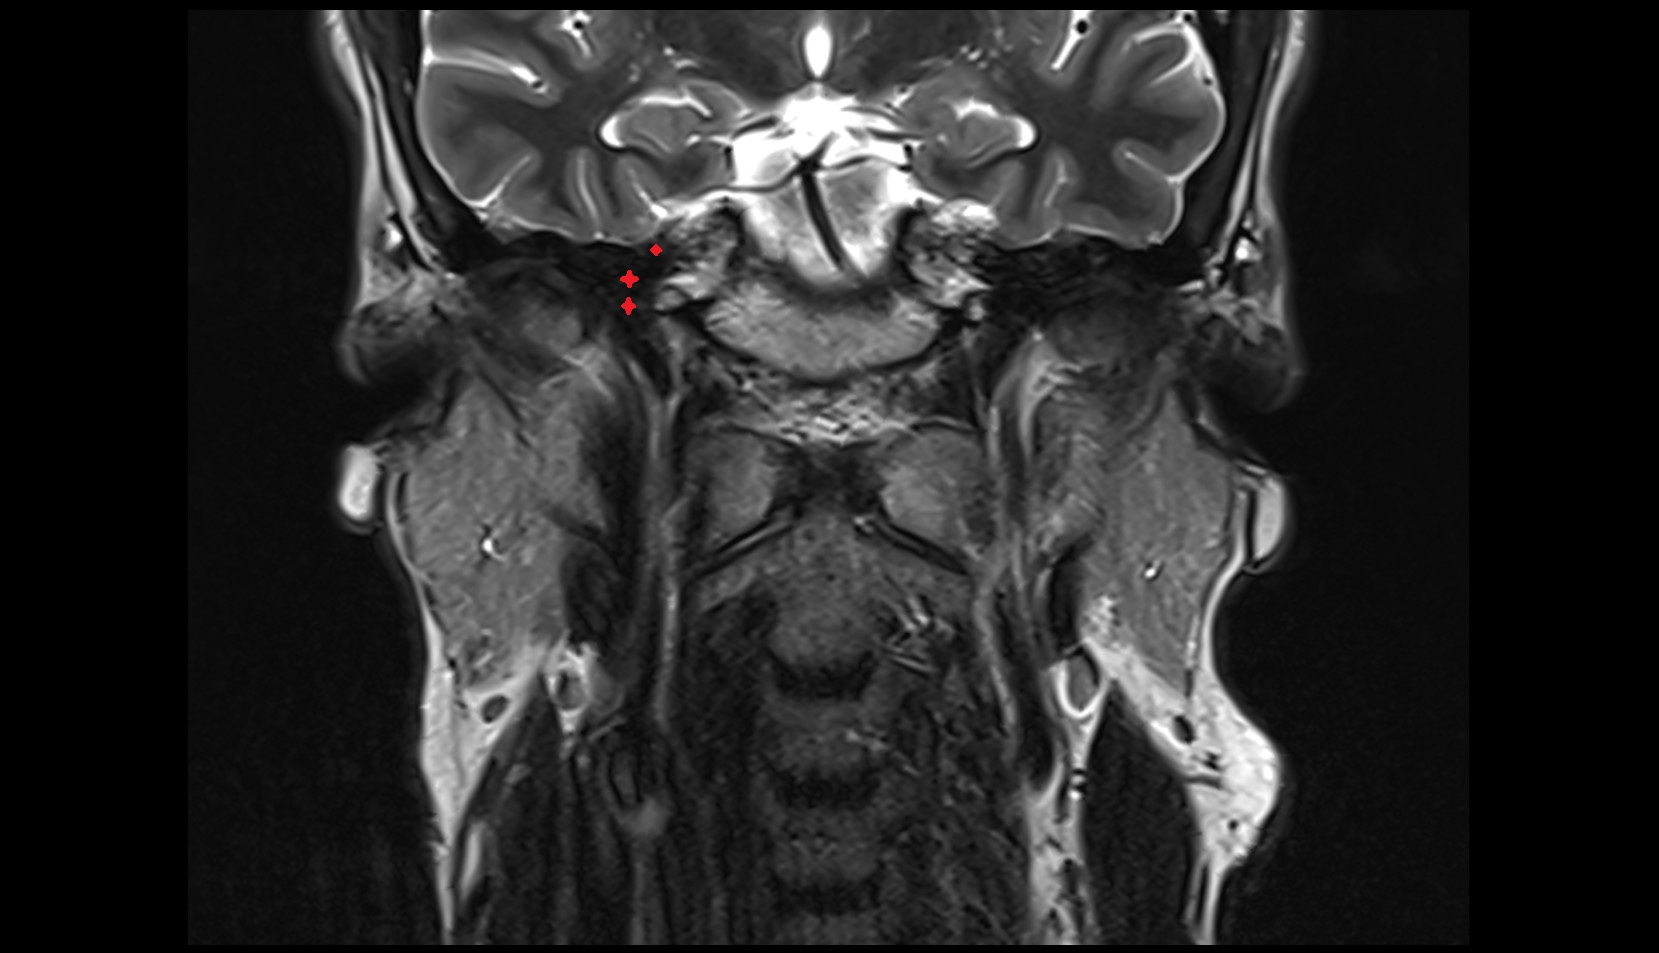

- Temporomandibular joint

- Mandibular condyle

- Mandibular fossa